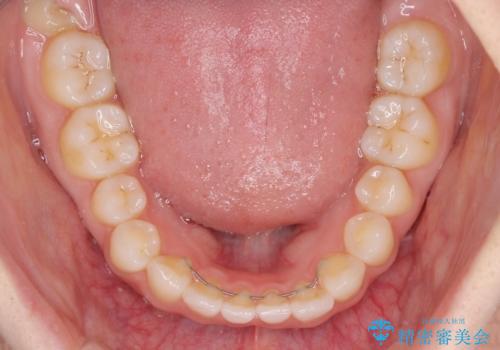

欠損による前歯のスペースが大きかったため、事前にワイヤー矯正で前歯の位置を大きく動かし、その後は上下をインビザラインで整えることとしました。

矯正治療後には欠損部はオールセラミックブリッジに、矮小歯はオールセラミッククラウンにて補綴することとしました。

ワイヤー矯正により、インビザラインよりも早く、歯軸の向きもコントロールしながら移動させることができました。